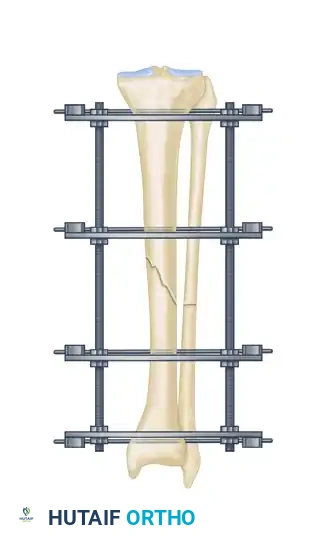

The management of complex, comminuted, or open tibial shaft fractures presents a formidable challenge to the orthopedic surgeon. The Ilizarov external fixation system, pioneered by Professor Gavriil Ilizarov, revolutionized the treatment of these injuries by introducing the concept of the tension-stress effect. Unlike rigid internal fixation, the Ilizarov circular frame utilizes tensioned fine wires to provide exceptional shear and torsional stability while permitting controlled axial micromotion. This unique biomechanical environment stimulates robust secondary bone healing (callus formation) without the need for extensive soft tissue stripping at the fracture site.

This comprehensive guide details the surgical technique for applying an Ilizarov external fixator to tibial shaft fractures, expanding upon foundational operative principles to provide a masterclass in frame assembly, multi-planar fracture reduction, safe-zone wire insertion, and the management of postoperative complications.

Surgical Technique: Step-by-Step Application

Step 1: Frame Preparation and Initial Placement

The Ilizarov frame is typically preassembled prior to the induction of anesthesia, based on preoperative measurements of the patient's limb.

- After meticulously preparing and draping the extremity, disconnect the ring connection bolts on one side of the preassembled frame to open it.

- Place the opened frame around the injured extremity.

- Reassemble the frame, ensuring adequate soft tissue clearance circumferentially. A general rule is to maintain at least two fingerbreadths (approximately 2 to 3 cm) of clearance between the skin and the inner border of the rings to accommodate postoperative edema.

- Align the frame so that the longitudinal coupling bolts are parallel to the anterior crest of the tibia in both the AP and lateral planes.

Step 4: Eliminating Residual Distraction

Following multi-planar correction, it is imperative to assess the fracture site for any residual longitudinal distraction. Distraction gaps inhibit secondary bone healing and lead to nonunion. Adjust the longitudinal threaded rods to compress the fracture site and eliminate any residual distraction.